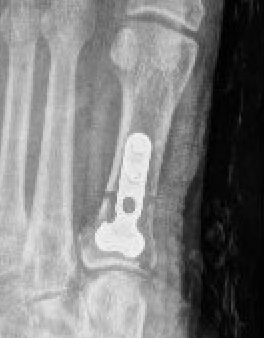

Stage 4 Tibialis posterior dysfunction

Hindfoot fusion

www.boneschool.com/pantalar-fusion

Triple Arthrodesis

Technique

Fixation - screws / plates / staples